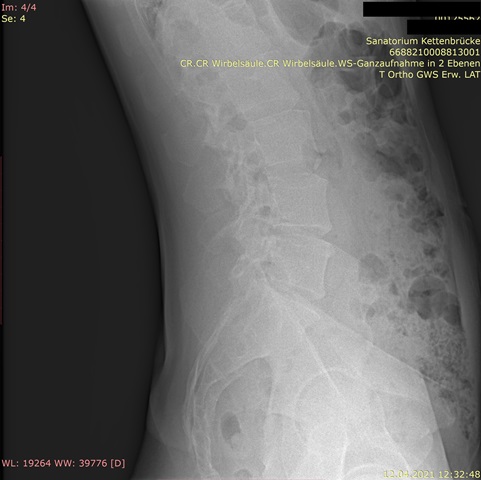

Habe die Bilder. Für mich als Laie sieht es nicht so schlimm aus auf den Röntgenaufnahmen, aber ich bin in der Realität total asymmetrisch und schief, und am extremsten ist, dass die Rippen/Brustkorb auf der rechten Seite viel mehr rausstehen und das optisch sehr auffällt.

Im Anhang die Bilder.

Ich (auch Laie) sehe nur eine geringe Seitabweichung der Wirbelsäule, aber eine deutliche Rotation, erkennbar an den "Kringeln" der Dornfortsätze und Querfortsätze. Ich denke auch, dass da ein Spezialist gefragt ist.rudi777 hat geschrieben: ↑Do, 22.04.2021 - 16:20 Für mich als Laie sieht es nicht so schlimm aus auf den Röntgenaufnahmen, aber ich bin in der Realität total asymmetrisch und schief, und am extremsten ist, dass die Rippen/Brustkorb auf der rechten Seite viel mehr rausstehen und das optisch sehr auffällt.